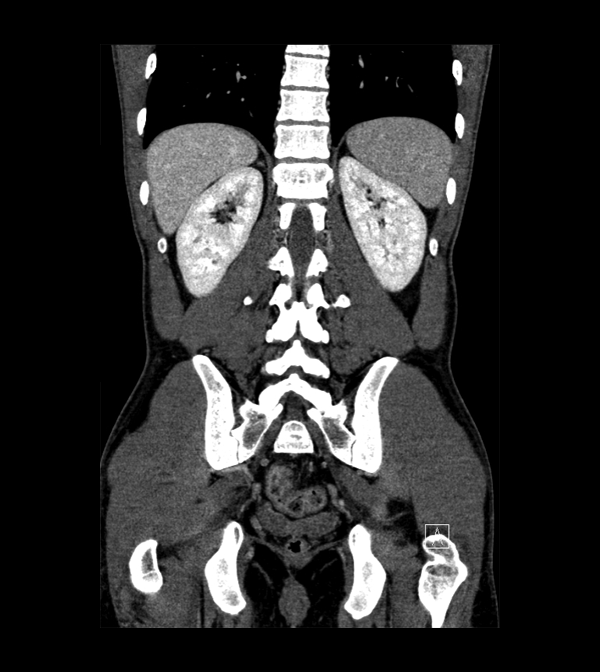

Body

Covers abdominal CT anatomy.